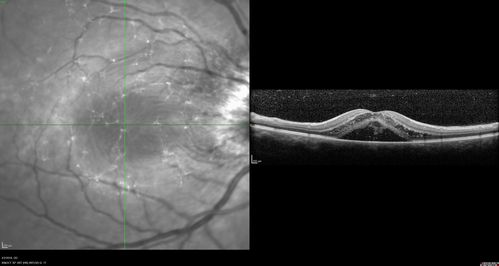

Cat Scratch - Neuroretinitis OD AND retinitis OS - Bartonella henselae positive

27 year old female with exposure to cats and prior fever.  Reports with recent vision loss right eye.  She was treated with doxycycline and within 2 weeks the right eye looks better.  Then she skipped all follow-up visits.  The right eye presented 20/200 and the left 20/16